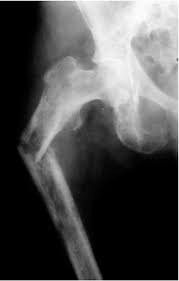

Son aquellas que ocurren entre la epífisis proximal del fémur y un plano ubicado por debajo del trocánter menor. De acuerdo con el nivel de la fractura, se clasifican en:

- Fracturas del cuello del fémur: aquéllas ubicadas entre un plano inmediatamente por debajo del límite del cartílago de crecimiento y el plano en que el cuello se confunde con la cara interna del macizo trocantereano.

- Fracturas pertrocantereanas: son aquéllas que cruzan oblícuamente el macizo troncantereano, desde el trocánter mayor al menor.

- Fracturas subtrocantéreas: ubicadas en un plano inmediatamente inferior al trocánter menor.

1. Clasificación anatómica: está determinada por el nivel de la línea de fractura. Así se las clasifica en:

- Fractura sub-capital: aquella producida en un plano inmediatamente inferior al del borde del cartílago de crecimiento; generalmente tiene una orientación algo oblícua, de modo que compromete un pequeño segmento del cuello del fémur. Son las más frecuentes.

- Fractura transcervical (o medio cervical): el rasgo compromete la parte media del cuerpo del cuello femoral.

Fractura basi-cervical: el rasgo de fractura coincide con el plano de fusión de la base del cuello en la